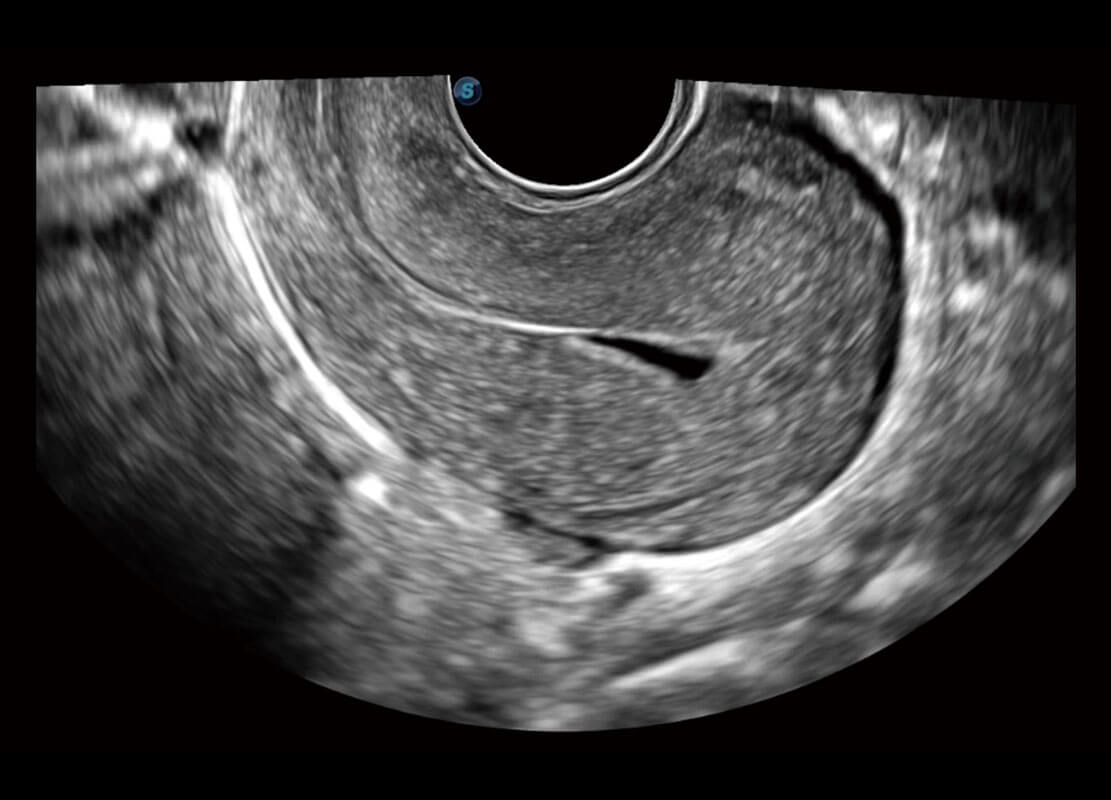

P60优异的图像质量搭载专科探头,在妇科基础疾病的诊断、卵泡生长的监测、输卵管通畅情况的判别等方面为您提供生殖应用方案。

腔内妇科-宫腔分离

腔内妇科-卵巢

腔内三维-宫内节育器